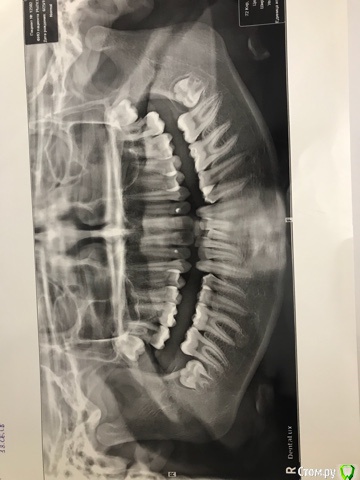

В 15 лет поехали на консультацию в ФГУ ЦНИИСиЧЛХ, диагноз: сочетанная скелетная деформация челюстей, верхняя прогнатия, нижняя ретромикрогнатия, дистальная оклюзия, глубокая резцовая дизокклюзия, сагитальная щель 10 мм, сужение деформация зубоальвеолярных дуг, скученное положение зубов, протрузия резцов, аномалия положения зачатков 8 моляров, уздечки нижней губы, мелкое предверие рта, индивидуальная макродентия.

Через два месяца планируется снятие брекетов. На выходе имеем: профиль лица выпуклый, некрасивый, но по сравнению с тем, что было улучшен. Сагитальная щель 3мм. На нижней челюсти оголились корни передних резцов. Были на консультации у хирургов, назначили день операции по уздечке нижней губы, которая даёт натяжение, но в день операции проводить не стали, сказали - лучше после снятия брекетов, чтобы не травмировать десну перед снятием. Озвучили про подвижность нижних зубов и выход корней из костной ткани. Рекомендовано удаление 8-к.

По поводу верхних резцов, до установки брекетов режущие края зубов были на одном уровне, видимо, ошибка в позиционировании брекетов, ТК в ходе лечения один верхний резец поднялся выше и отклонялся от вертикали, выровнять края не удалось, но ТК, как пишут, пациентов в первую очередь волнует косметика, дочка переживает, что очень бросается в глаза. Прочитала в интернете в блоге одного ортодонта, что такая ошибка исправляется либо изгибом дуги либо Переустановкой новых брекетов, поэтому он работает с брекетами средней ценовой категории и переустанавливает в случае отклонения. На этой неделе плановый прием у ортодонта, хочу предложить : переустановить на два верхних резца новые брекеты, а на нижней челюсти - принесу новый трг (прикреплен в предыдущем сообщении) и как-то надо решать проблему с выходом корней из кости, если такая действительно есть, ТК хирурги в направлении к ортодонту не написали такое, а только озвучили, а написали на консультацию по поводу удаления 8-к.

По месту жительства про сепарацию зубов никто из докторов не предлагал, но наш лечащий врач произвела сепарацию двух верхних резцов и сказала, что надо бы ещё, но мы как-то боимся, ТК укрепление эмали после сепарации не проводилось.